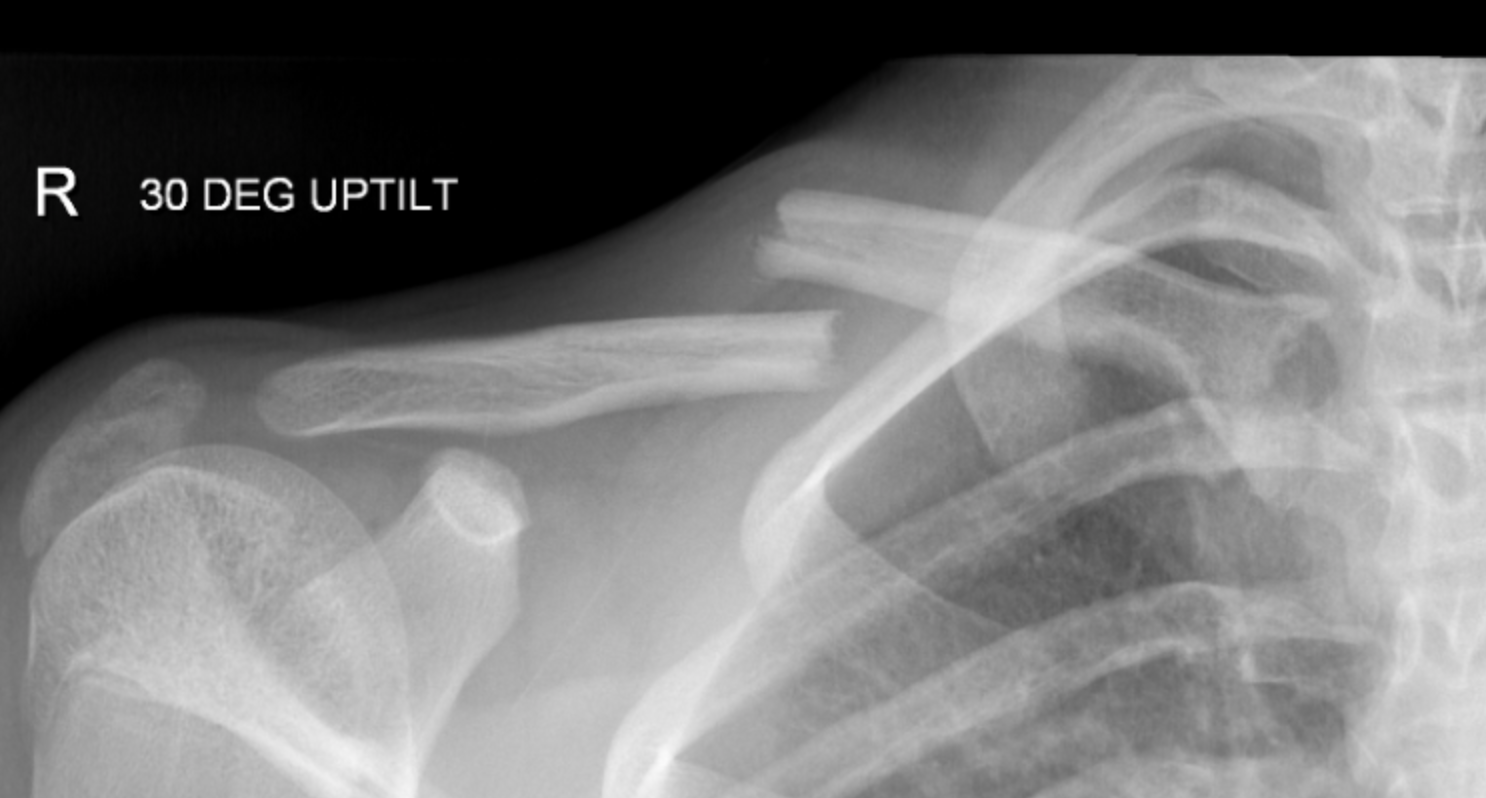

clavicle fracture

shoulder girdle (acromioclavicular joint)

acromicalvicular (AC) joint

plantar type joint between lateral portion of the clavicle and the acromion of the scapula